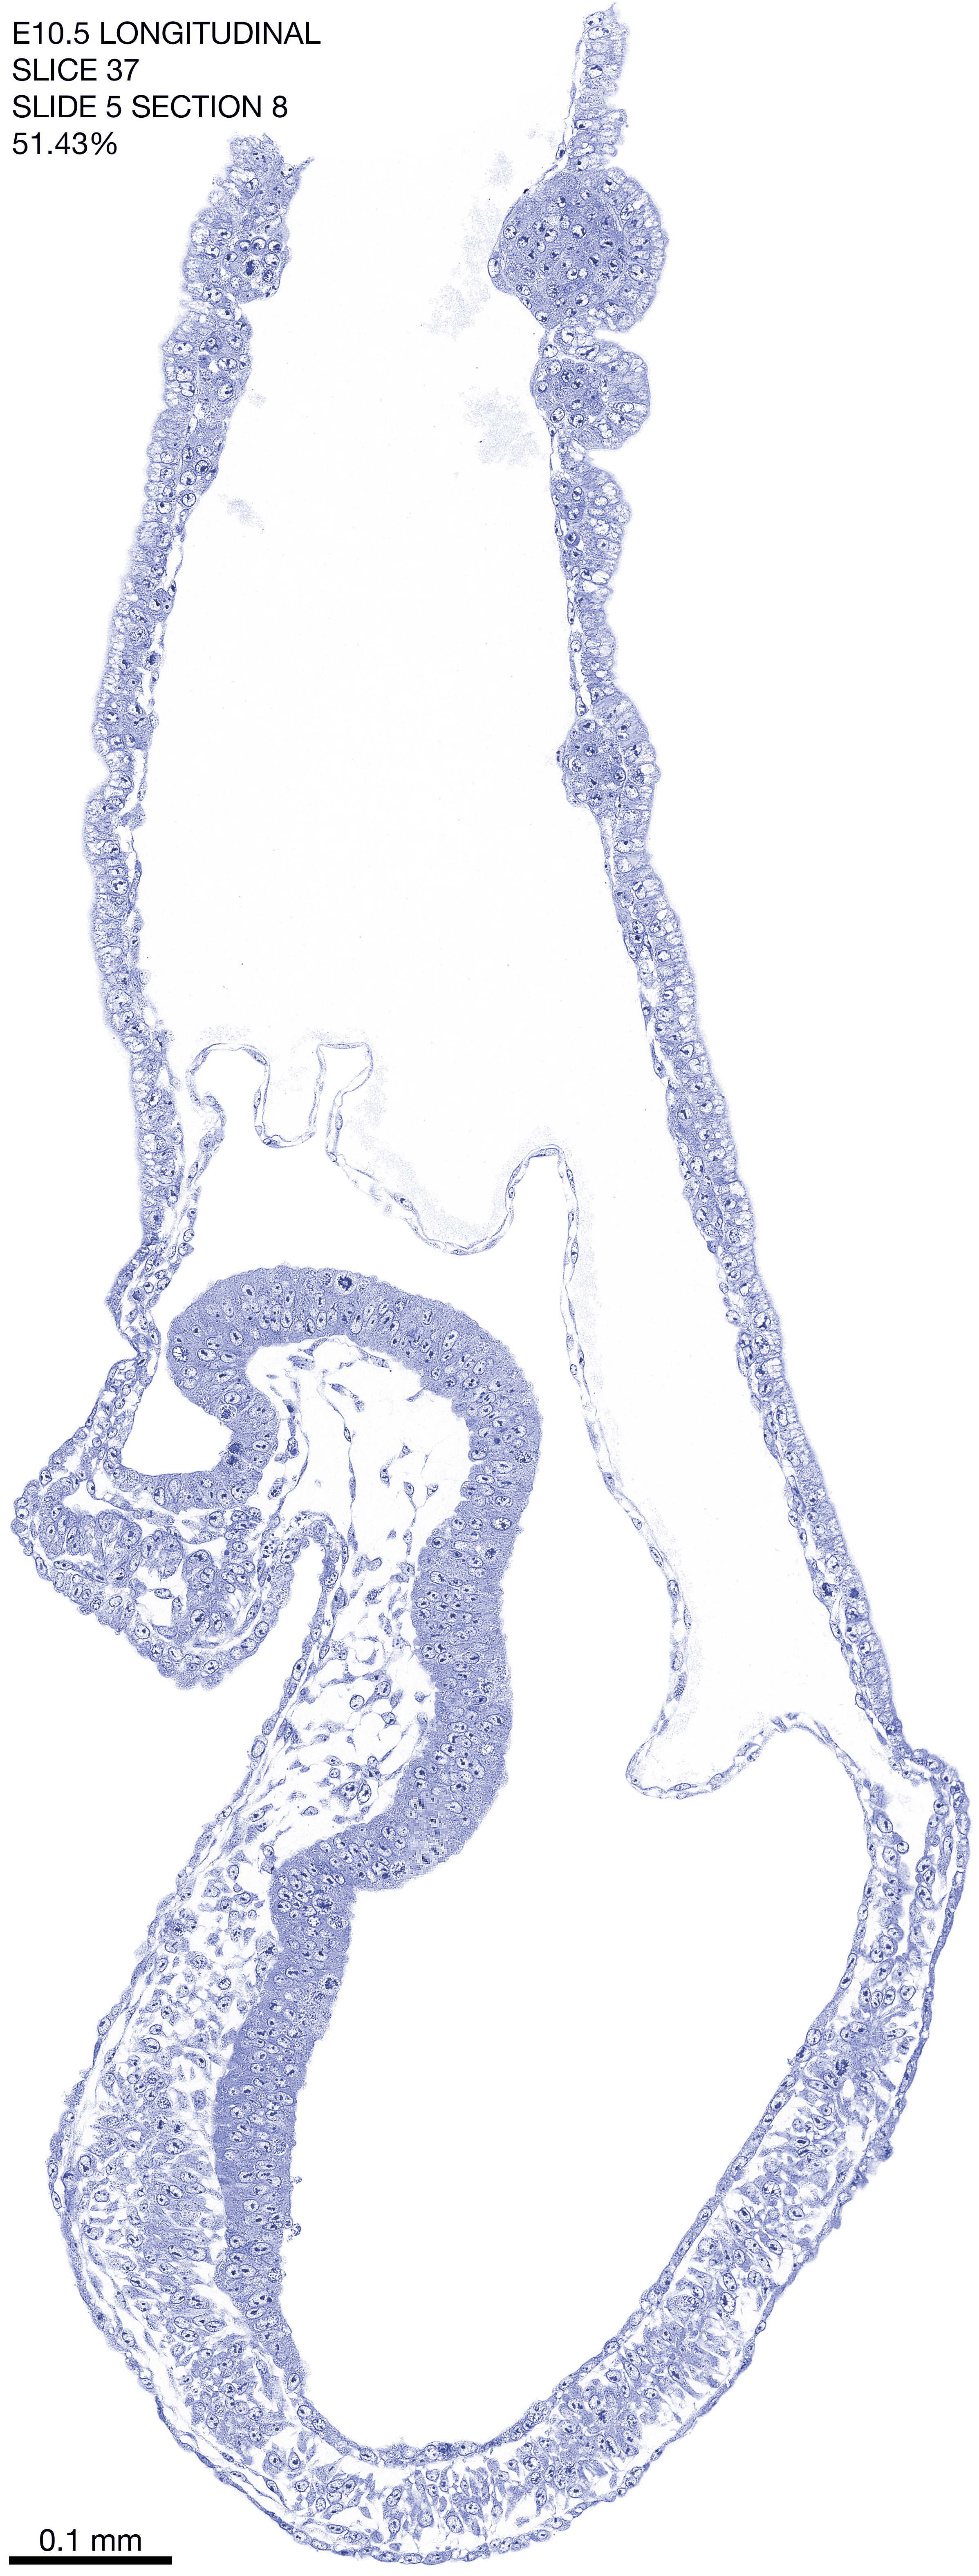

E10.5 Longitudianal Archive This page contains jpg files of ALL SLICES (each 3µm thick) that were scanned of the E10.5 longitudinally cut specimen. Download: Large | High Res Download: Large | High Res Download: Large | High Res Download: Large | High Res Download: Large | High Res Download: Large | High Res Download: Large | High Res Download: Large | High Res Download: Large | High Res Download: Large | High Res Download: Large | High Res Download: Large | High Res Download: Large | High Res Download: Large | High Res Download: Large | High Res Download: Large | High Res Download: Large | High Res Download: Large | High Res Download: Large | High Res Download: Large | High Res Download: Large | High Res Download: Large | High Res Download: Large | High Res Download: Large | High Res Download: Large | High Res Download: Large | High Res Download: Large | High Res Download: Large | High Res Download: Large | High Res Download: Large | High Res Download: Large | High Res Download: Large | High Res Download: Large | High Res Download: Large | High Res Download: Large | High Res Download: Large | High Res Download: Large | High Res Download: Large | High Res Download: Large | High Res Download: Large | High Res Download: Large | High Res Download: Large | High Res Download: Large | High Res Download: Large | High Res Download: Large | High Res Download: Large | High Res Download: Large | High Res Download: Large | High Res Download: Large | High Res Download: Large | High Res Download: Large | High Res Download: Large | High Res Download: Large | High Res Download: Large | High Res Download: Large | High Res Download: Large | High Res Download: Large | High Res Download: Large | High Res